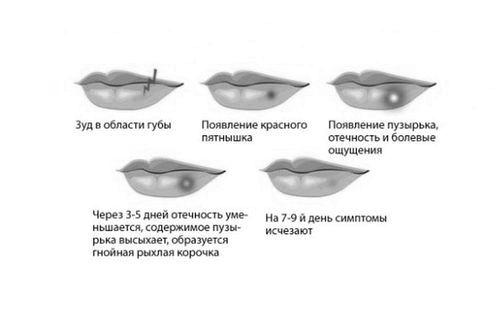

герпес губ

Самий легко впізнаваний вигляд хвороби. Має візуальні симптоми і характеризується погіршенням самопочуття.

симптоматика

- Поява почуття слабкості.

- Відчуття сверблячки на обличчі.

- Почервоніння ділянок тіла і поява в них хворобливих відчуттів.

- Прояв бульбашки, що має всередині прозору рідину - герпес.

- Освіта виразки після розриву оболонки бульбашки.

- Можливе підвищення температури.

- Іноді турбує головний біль.

Після того як пляшечку з рідиною розірвався, вірусні частинки починають стрімко поширюватися не тільки по тілу хворої жінки, а й заражаючи інших людей. Новоутворена виразка дуже часто травмується або здирається, приводячи до синців і рані. Якщо вчасно не обробляти такі ознаки розвитку хвороби, це може привести до зараження крові.

Зазвичай герпес на губах заживає протягом 10 діб, але якщо цей процес триває довше, необхідно терміново проконсультуватися з дерматологом, який призначить ефективне лікування.